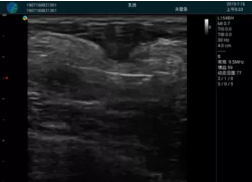

清晰顯示腺體內低回聲快影,邊界清晰,包膜較光滑

確定進針路徑并實時監(jiān)測抽吸針與腫塊位置關系

抽吸針進入腫塊內部進行旋切

抽吸過程中可見腫塊明顯縮小,并根據腫塊位置改變針道位置

抽吸旋切后再進行超聲復查,原腫塊區(qū)域未見殘留組織及出血